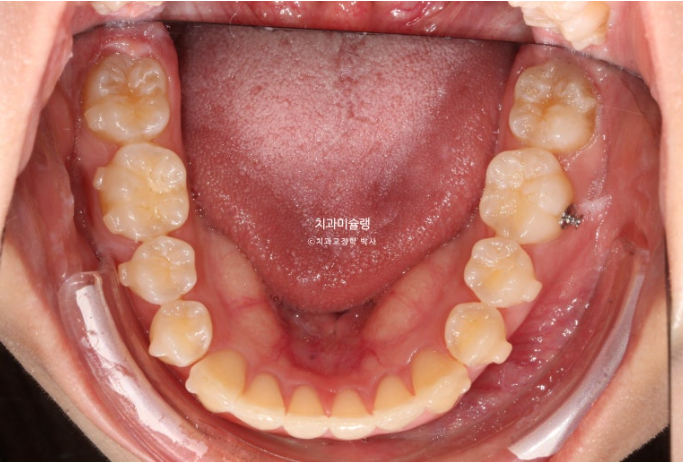

작년 1월, 앞니 덧니 교정을 위해 온 환자분입니다. 튀어나온 측절치 이외에는 신경쓰이는 부분은 없다고 하셨죠.

정면사진에서 블랙트라이앵글, 중심선 불일치 등이 보입니다.

덧니쪽으로 중심선은 치우치기 마련이지만 그 이외에도 양쪽 어금니 교합관계가 다르다 보니 중심선 불일치가 크게 나타납니다.

양측 어금니 교합관계를 정확히 1급으로 맞춰 중심선까지 정확히 일치시키는 치료계획은 일년반의 시간이 소요되며 인비절라인 컴프레헨시브 프로그램이 필요합니다.

환자분은 덧니 개선에만 초점을 둔 짧고 간단한 치료를 원했고 인비절라인 라이트로 치료하기로 했습니다.